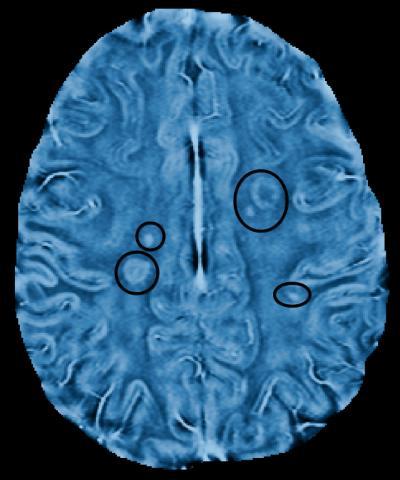

This brain image was developed using a frequency-based MRI scan. The circled areas show lesions -- scars in the myelin.

(Photo Credit: Alex Rauscher/University of British Columbia)

Alex Rauscher, assistant professor of radiology at the University of British Columbia, has shown that a frequency-based MRI scan reveals myelin damage in MS patients in finer detail than ever before.

Once scars in the myelin, known as lesions, appeared in conventional MRI scans, Rauscher and his colleagues went back to earlier frequency-based images of those patients. Looking in the precise areas of those lesions, they found frequency changes – indicating tissue damage – at least two months before any sign of damage appeared on conventional scans. The results were published according to research published in the June 12, 2013, issue of Neurology®, the medical journal of the American Academy of Neurology.